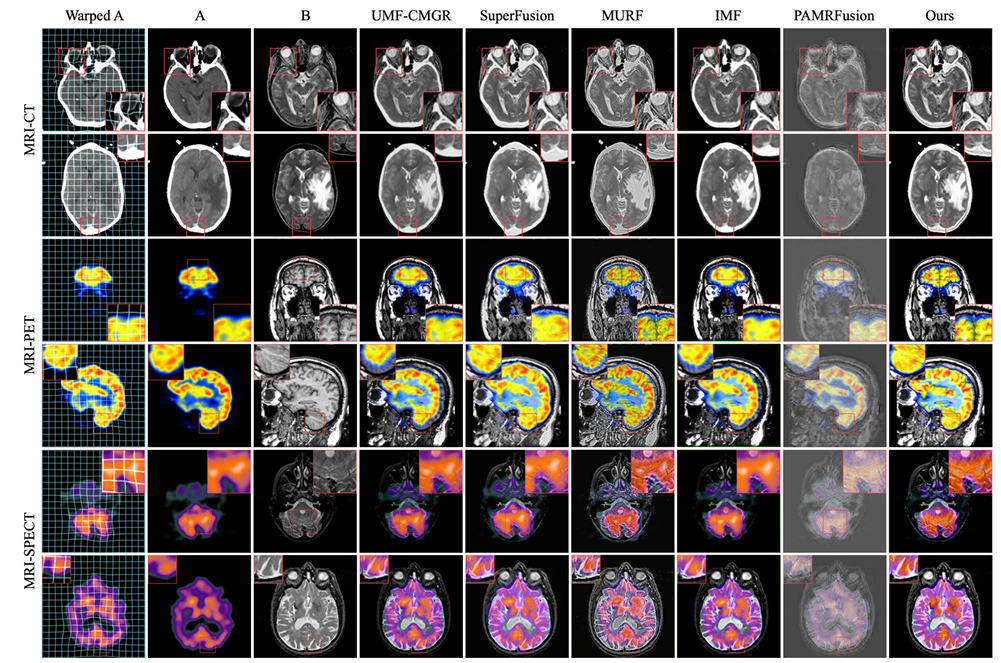

实验的比较对象是目前最先进的 5 种联合配准方法,包括 UMF-CMGR 、 superFusion 、 MURF 、 IMF 和 PAMRFuse 。其中除最后一组外,前 4 个均为非专门为多模态医学图像融合设计的方法,但已是目前最优的图像融合方法,且适用于 MMIF 。如下图所示:

结果明显,课题组所提的方法在特征对齐、对比度保持和细节保留等方面均呈现出比之更强的优越性,且所有指标中平均性能最佳。